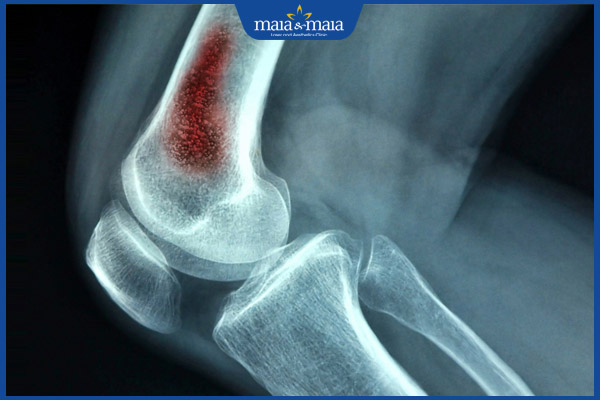

- Viêm xương và tủy xương: Nhiễm trùng lan đến xương gây viêm xương mãn tính, khó điều trị và có nguy cơ để lại di chứng lâu dài.